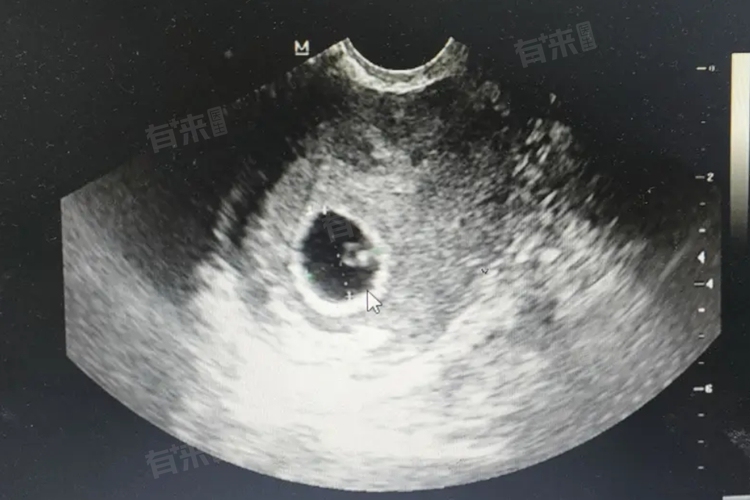

- 胚胎形成始于受精卵,受精卵在输卵管内向子宫移动过程中,不断进行有丝分裂,形成多个细胞的桑椹胚。随后,细胞继续分裂并开始分化,形成囊胚,囊胚包含内细胞团和滋养层细胞。内细胞团将发育成胎儿的各种组织器官,滋养层细胞则负责与母体子宫建立联系,为胚胎获取营养、氧气并排出代谢废物,这一过程在受精后的数周内迅速进行。

- 胚胎发育有多个关键时期,在受精后的1-2周,受精卵着床是重要节点,若着床失败则可能导致妊娠失败。孕早期3-8周是器官形成的关键阶段,此时胚胎对各种致畸因素极为敏感,如药物、辐射、病毒感染等都可能干扰器官正常发育,导致先天性畸形。如心脏在第3周开始发育,神经管在第4周闭合,任何干扰因素在此期间作用都可能产生严重后果。